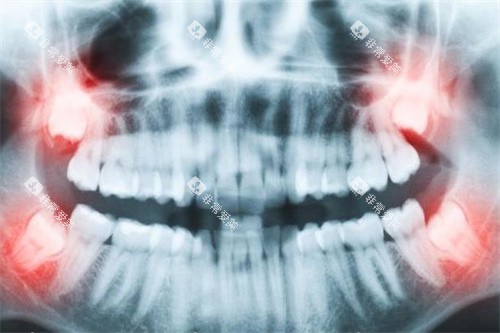

在进行具体的牙齿治疗之前,通常需要可靠行牙齿检查与诊断。

承德市中心医院牙科会通过多种方式对患者的牙齿状况进行超全评估。

一般的口腔检查,包括医生对牙齿外观、牙龈状况等进行直观检查,收费相对较为便宜,大约在 20 - 50 元左右。

如果需要进行更详细的检查,如口腔X光片拍摄,根据拍摄部位和类型的不同,价格也有所差异。

全景X光片的收费大概在 100 - 200 元,而根尖片每张可能在 20 - 50 元。

对于一些复杂的病例,可能还需要进行 CT 检查,费用可能在 300 - 800 元不等。

这些检查费用主要用于帮助医生比较准了解患者的牙齿问题,为后续的治疗方案制定提供依据。